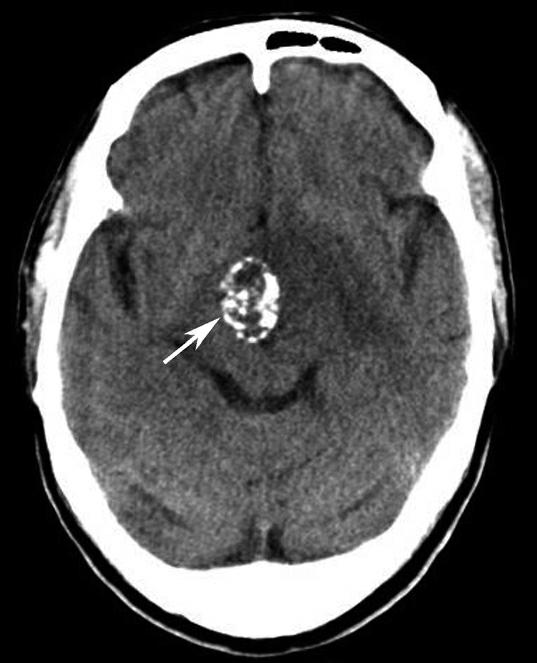

图1-2-27 松果体肿瘤

A.松果体生殖细胞瘤,表现为均质高密度影(★),箭头所指高密度影为脑室内引流管断面;B.松果体囊肿,表现为边界清楚之低密度影(☆)

松果体、苍白球在成人期常出现钙化,属生理性钙化,一般无病理意义。需注意勿误诊为出血灶,尤其是单侧苍白球钙化时(图1-2-28)。

图1-2-28 苍白球生理性钙化

A.双侧苍白球对称性钙化,呈高密度影(箭);B.左侧苍白球钙化(箭),右侧苍白球钙化不明显